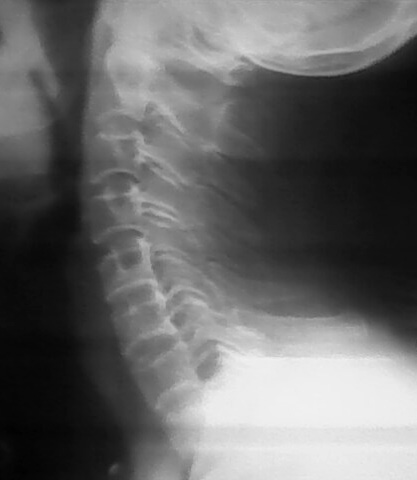

以下是引用jiangguowu在2009-8-26 21:28:00的发言:[br]加照对侧斜位,没有的话考虑软组织钙化或体外异物,如有则考虑椎后韧带钙化或游离髓核钙化